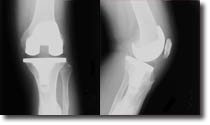

Now, let’s go backwards to bring you up to date on other parts of our cruisin’ life. January 26th Gary had total knee replacement surgery at Harrison Hospital in Bremerton spending four days in the hospital before transferring to Martha & Mary Health Center in Poulsbo for rehabilitation. His surgery went very well and he was soon walking down the halls at Martha and Mary with only a cane. In less than two weeks after his surgery he was home. We were amazed at how quickly he was able to maneuver on the boat. Dr. Brad Watters was his surgeon and is well known in this area for his expertise and use of technology, Gary was able to get all his X-rays on CD, and so he decided to include this picture of his new knee.